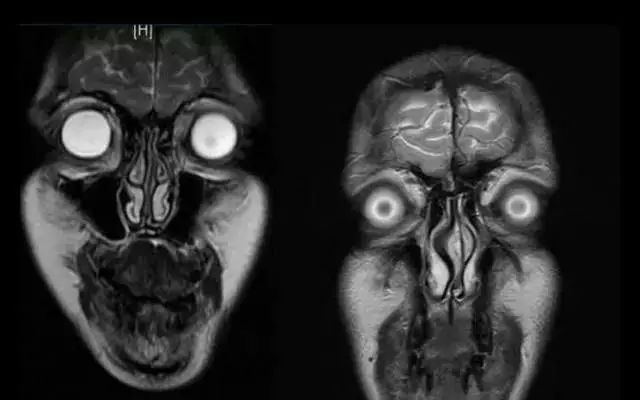

正如上面这张图一样

我们每个人在 MR 下都是这样『狰狞』

而且你会发现

小小一张脸,黑影咋就这么多!

其实那都是

我们的呼吸或其他小动作

导致身体轻微偏移造成的『伪影』

这些影子

可能会影响到医生的诊断

有些病变可能还会看不出来